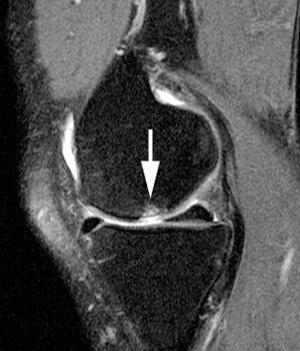

<¹«¸­°üÀý¿° X-RAY / MRI>

¹«¸­¿¬°ñÀÇ ¼Õ»ó ¶Ç´Â ÅðÇ༺ º¯È­·Î ÀÎÇØ °üÀýÀ» ÀÌ·ç´Â »À¿Í ÀÎ´ë µî¿¡ ¼Õ»óµîÀ¸·Î ÀÎÇÏ¿© ¿°Áõ°ú ÅëÁõÀÌ »ý±â´Â °æ¿ì¸¦ ¹«¸­ °üÀý¿°À̶ó°í ÇÕ´Ï´Ù. ¹«¸­°üÀý¿°Àº 55¼¼ ÀÌ»óÀÎ °æ¿ì¿¡´Â ¾à 80£¥, 75¼¼ÀÎ °æ¿ì¿¡´Â °ÅÀÇ Àü Àα¸¿¡ ¹ßº´Çϰí ÀÖ°í ³²¼ºº¸´Ù´Â ¿©¼º¿¡°Ô ´õ ¸¹ÀÌ ³ªÅ¸³ª¸ç ±× Á¤µµµµ ½ÉÇÕ´Ï´Ù. ¶ÇÇÑ ºñ¸¸ÁõÀÌ ÀÖ´Â °æ¿ì³ª °ú°Å¿¡ ±³Åë»ç°íŬ¸®´ÐÀ̳ª ¿Ü»óÀ¸·Î ÀÎÇÏ¿© »À³ª °üÀýÀÌ ´ÙÃÆ´ø °æ¿ì, ¼±Ãµ¼º ±âÇüÀÌ ÀÖ´Â °æ¿ì, »À ´ë»ç¿¡ ÀÌ»óÀÌ ÀÖ´Â °æ¿ì, Á÷¾÷ ¶Ç´Â Ãë¹Ì·Î ÇÑ °üÀýÀ» °è¼ÓÇØ¼­ ¹«¸®ÇÏ°Ô »ç¿ëÇÏ´Â °æ¿ì¿¡µµ Àß ¹ß»ýÇÏ°Ô µË´Ï´Ù.